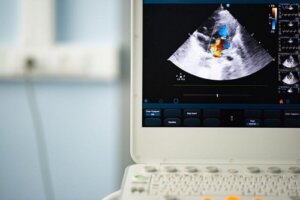

Podczas wizyty może wykorzystać stetoskop, aby usłyszeć nieregularne palpitacje serca oraz szmery w sercu. Następnie aby sprawdzić czy dana osoba cierpi na dwupłatkową zastawkę aorty, wykona echokardiogram, który pozwala zobaczyć, czy serce pracuje we właściwy sposób.

Poza tym wszyscy bliscy krewni osoby z dwupłatkową zastawką aorty powinni mieć zrobiony echokardiogram, aby upewnić się, że wszystko jest w porządku. Należy to zrobić, ponieważ krewni powinni się upewnić, że ich zastawki działają we właściwy sposób.